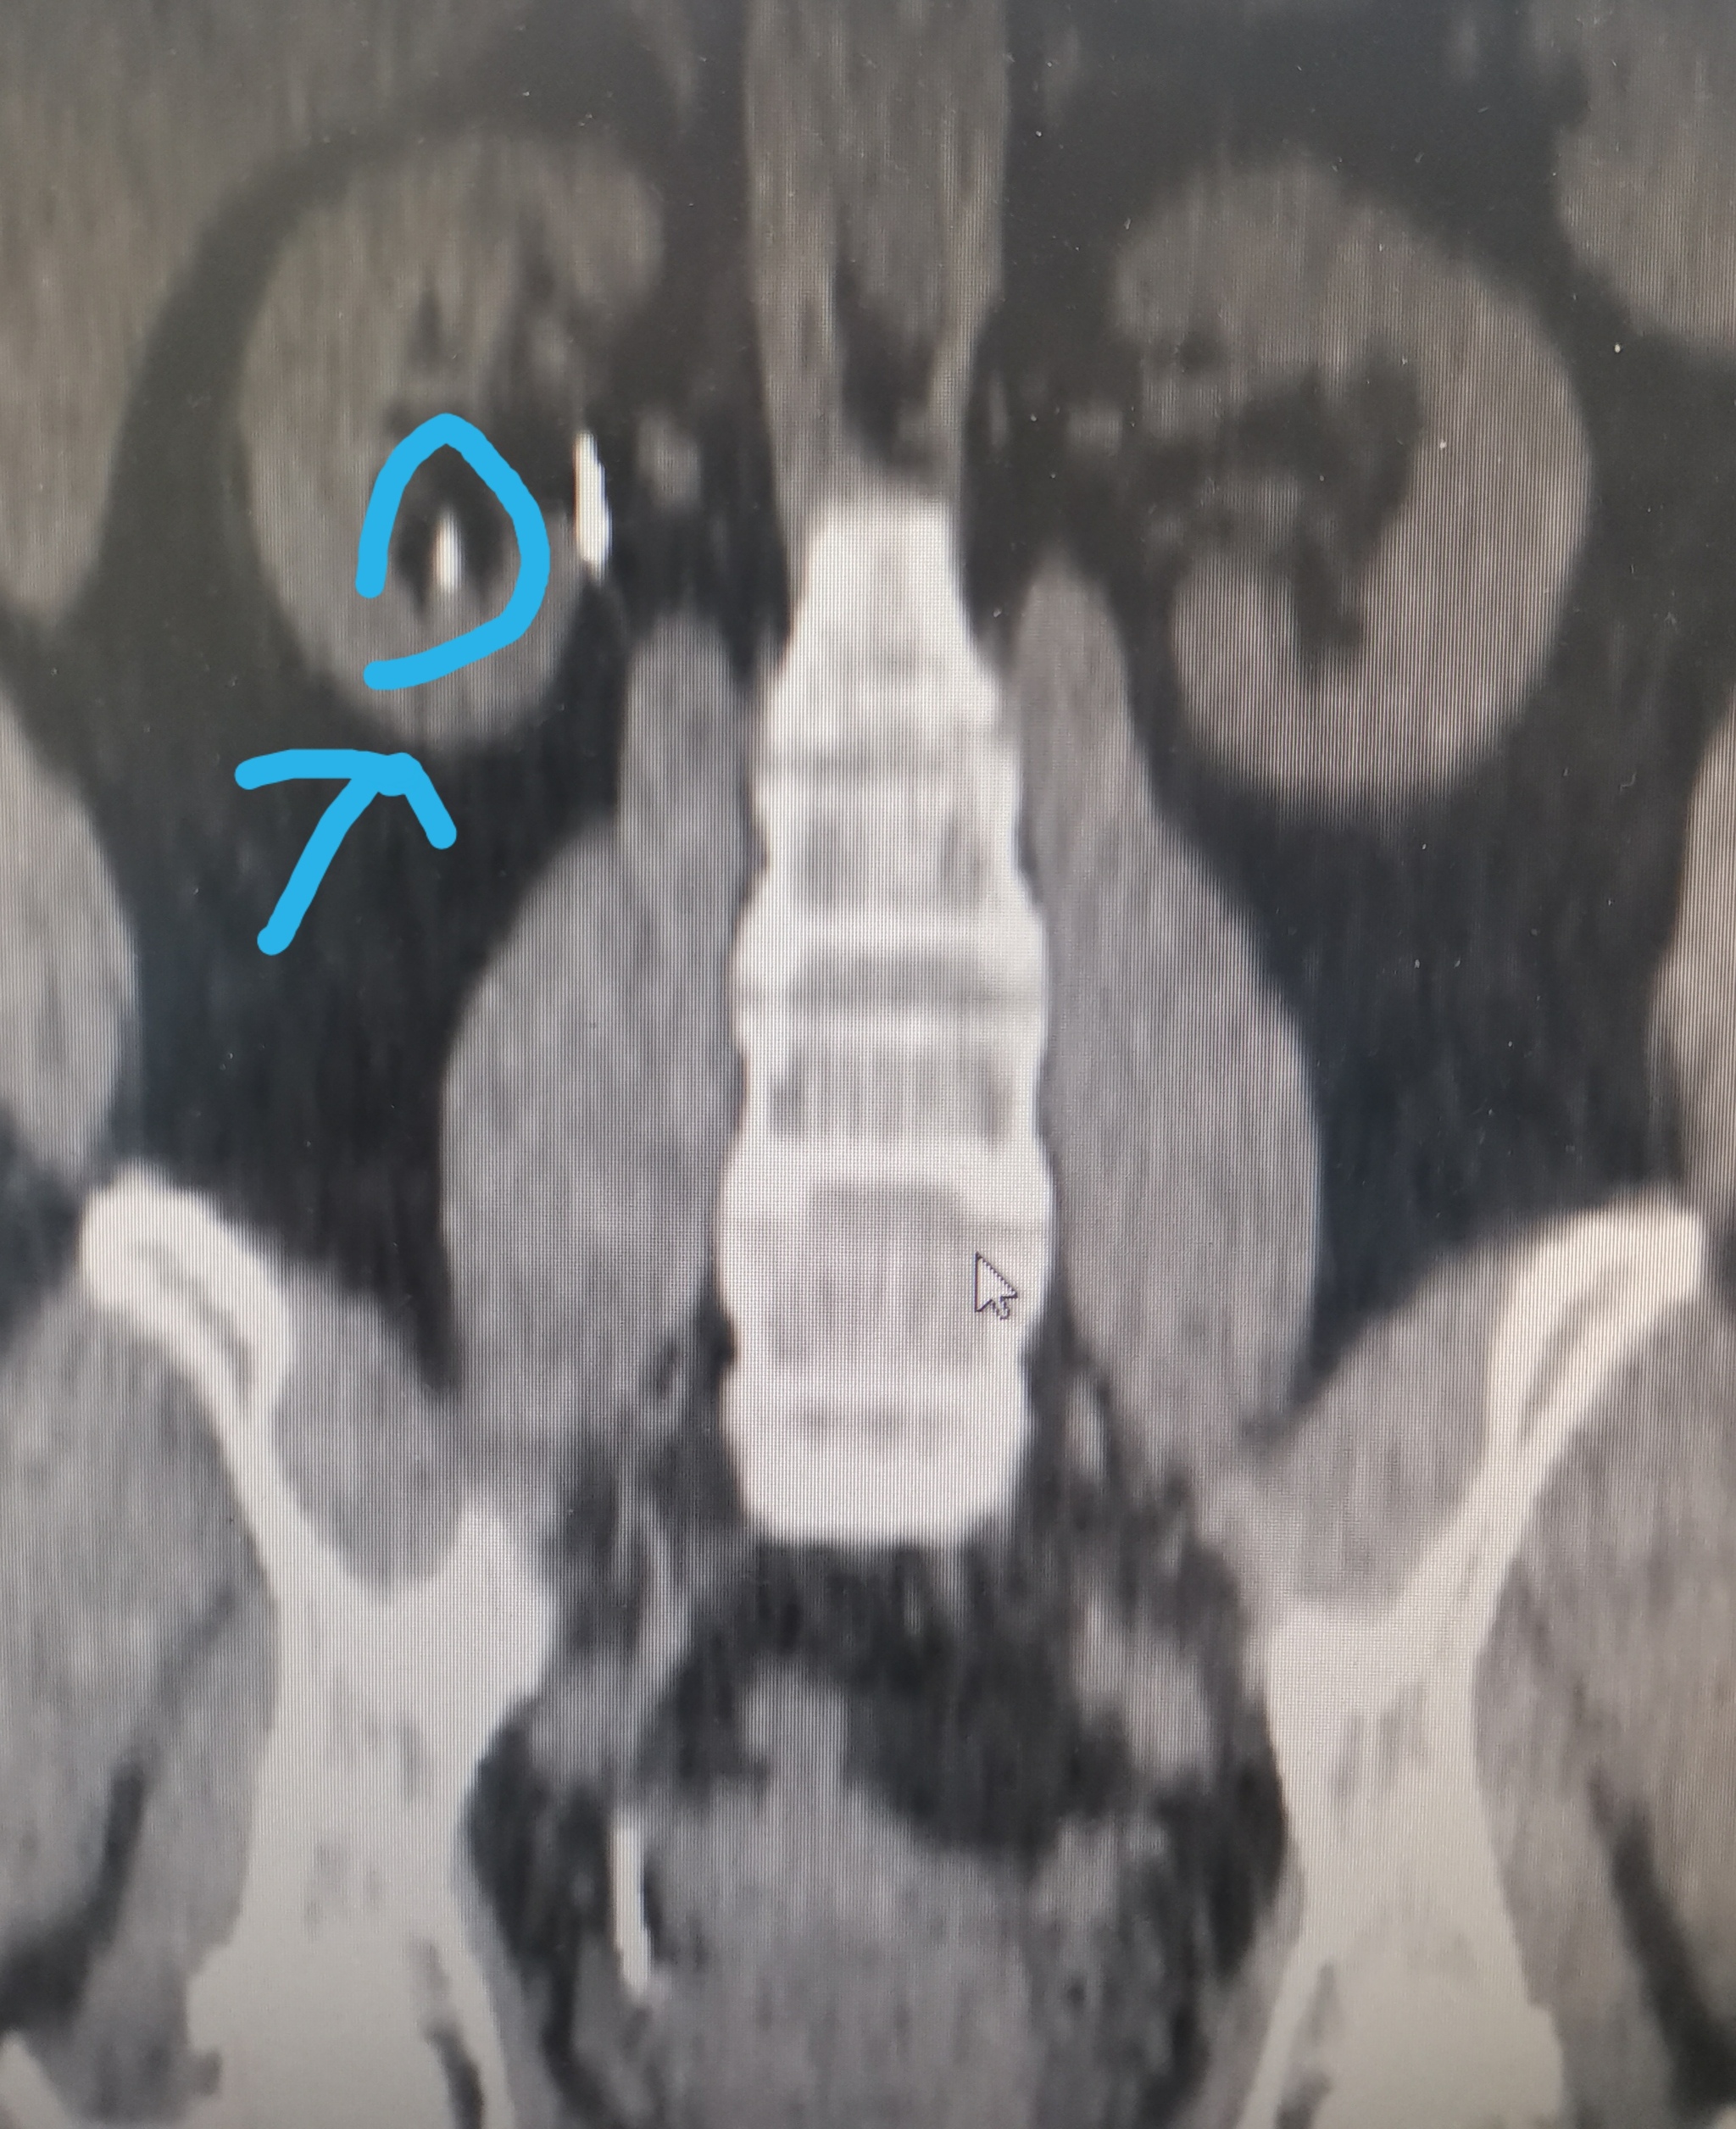

На УЗИ у меня не нашли камни, а на КТ (компьютерная томография) нашли камни в почках. Почему так?

При диагностике камней почек примерно до 1/3 случаев могут иметь погрешности (многое конечно будет зависеть от врача и качества аппарата). Особенно часто ошибки происходят, когда камни 3 мм и меньше. Камни 4-5 мм и больше все же хорошо видны на УЗИ.

Что же касается томографии, то КТ является "золотым стандартом" (эталонный метод) диагностики мочекаменной болезни. Его точность, специфичность доходит до 99%.